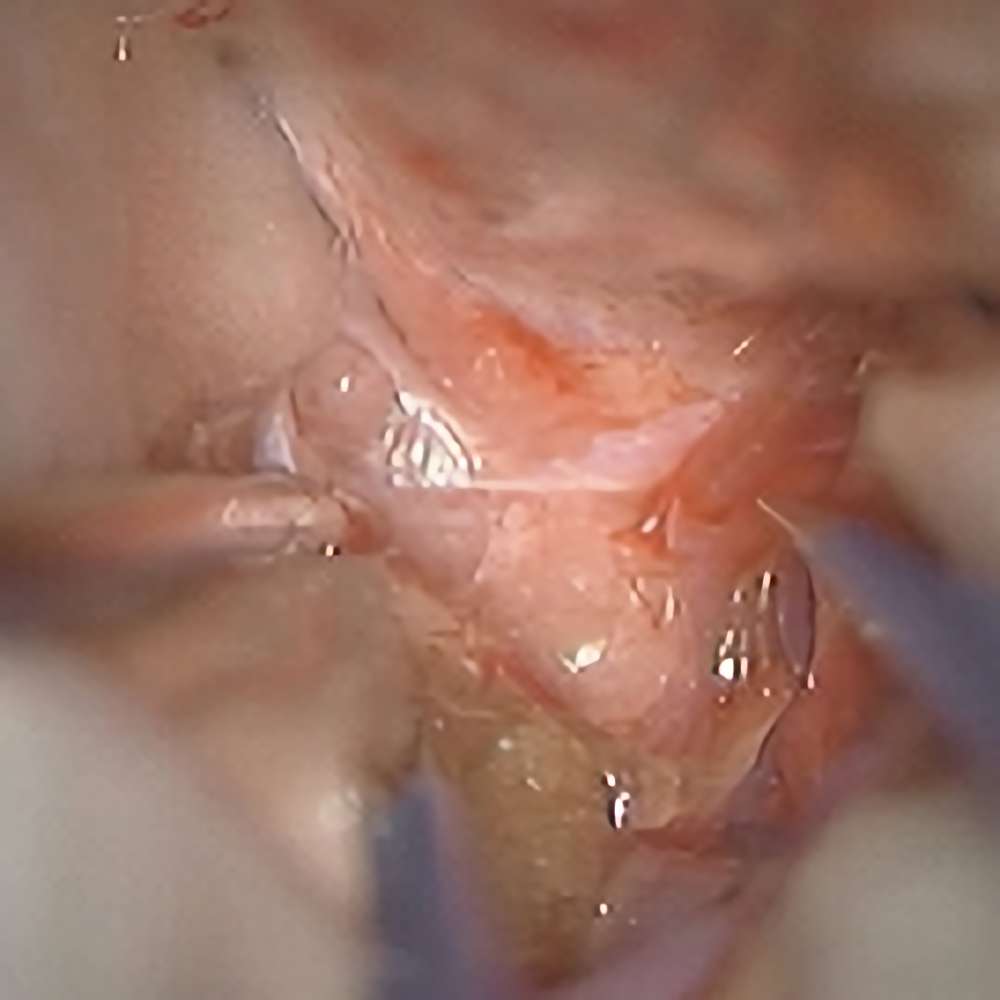

218

'21年9月

80代

左後頭頂葉腫瘤

頭蓋内腫瘍摘出術

No.’21_62 摘出 前

No.’21_62  摘出 中

No.’21_62 摘出 後